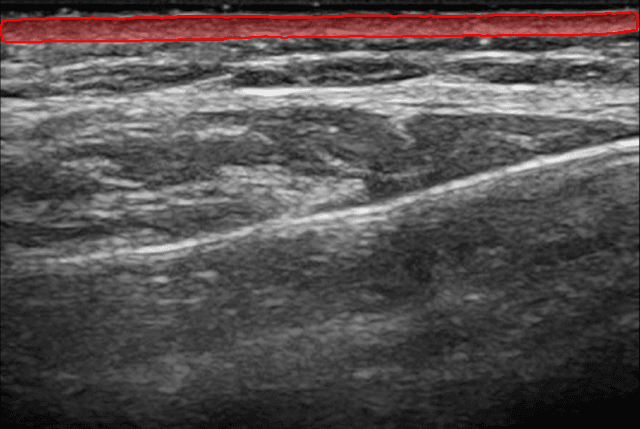

Nuestra IA segmenta instantáneamente tu capa dérmica. Obtén mediciones precisas de el grosor y el área de la dermis.